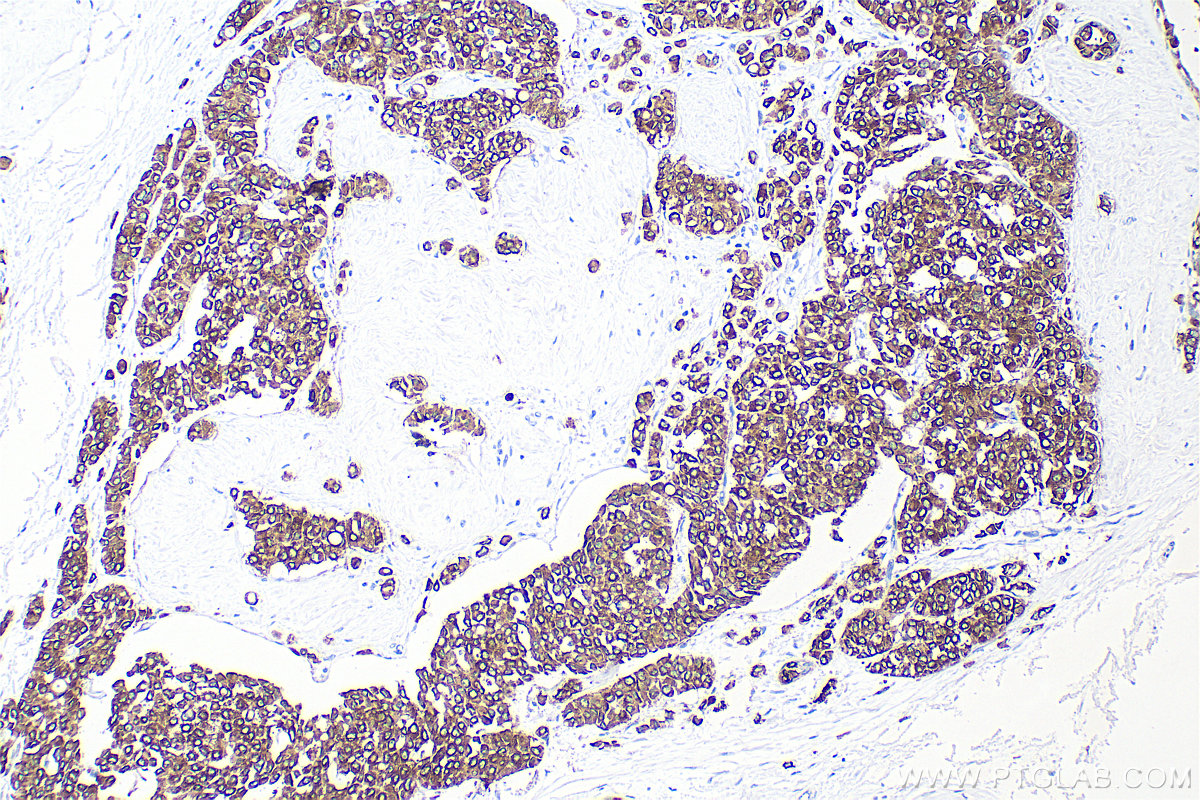

| Positive IHC detected in | human tonsillitis tissue, human appendicitis tissue, human bowen disease tissue, human breast cancer tissue, human colon tissue, human liver tissue, human renal cell carcinoma tissue Note: suggested antigen retrieval with TE buffer pH 9.0; (*) Alternatively, antigen retrieval may be performed with citrate buffer pH 6.0 |

Cytokeratin 8 (CK8) is a protein that belongs to the cytokeratin family, which is a group of structural proteins found in the intracytoplasmic cytoskeleton of epithelial cells. CK8 forms intermediate filaments within the cytoplasm of simple epithelial cells, typically as a dimer with cytokeratin 18 (CK18). These filaments provide a stabilizing framework that helps determine cell shape and enables cells to cope with mechanical stress. CK8/CK18 filaments also serve as a mesh of "paths" for signaling molecules, metabolites, and pathogens to travel within the cell in an organized manner. CK8 is expressed in various epithelial tissues and is particularly associated with glandular and simple epithelia. Its expression is also a significant marker in several types of cancer, including lung and esophageal cancer, where it can indicate tumor progression and poor prognosis.